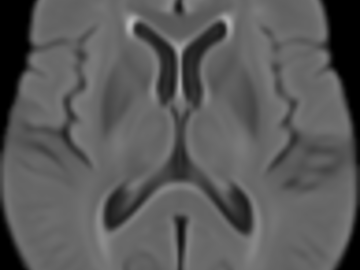

Normative brain atlases are a standard tool for neuroscience research and are, for example, used for spatial normalization of image datasets prior to voxel-based analyses of brain morphology and function. Although many different atlases are publicly available, they are usually biased with respect to an imaging modality and the age distribution. Both effects are well known to negatively impact the accuracy and reliability of the spatial normalization process using non-linear image registration methods. An important and very active neuroscience area that lacks appropriate atlases is lesion-related research in elderly populations (e.g. stroke, multiple sclerosis) for which FLAIR MRI and non-contrast CT are often the clinical imaging modalities of choice. To overcome the lack of atlases for these tasks and modalities, this paper presents high-resolution, age-specific FLAIR and non-contrast CT atlases of the elderly built from clinical images.

We provide an asymmetric and symmetric version of both the FLAIR and NCCT atlases in the standard MNI coordinate system with binary masks for the brain volume. We also provide the deformation field to map parcellations in the MNI space to our atlases (both symmetric and asymmetric) should researchers require this in their individual research projects.

FLAIR atlas NCCT atlas Deformation filesPublication: